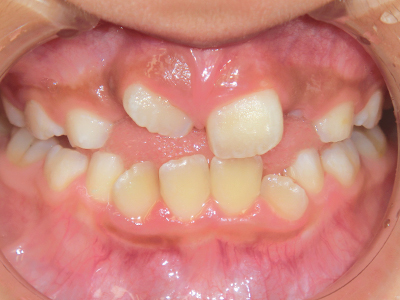

小児矯正について

「うちの子は矯正が必要なのだろうか?」

保護者の方が不安に思われたり、保育園・幼稚園・小学校などから歯科検診の結果票が届いたりした時点で、一度お子様連れでご来院ください。

お口を拝見し、矯正治療の要否や今後の受診についてお話しさせていただきます。

歯並びの相談に来られるお子様は、口呼吸をしているケースが多く、これが歯並びに大きな影響を与えています。

↓ - 上あごが狭くなる

↓ - 下あごが狭くなる・下あごの位置が悪くなる

↓ - さまざまな不正咬合が生じる

ないき歯科クリニックでは、上あごの成長不足を補い、鼻呼吸を獲得しつつ歯列を整え、将来のお口をより健康な状態にすることをゴールに定める矯正治療をおこなっています。